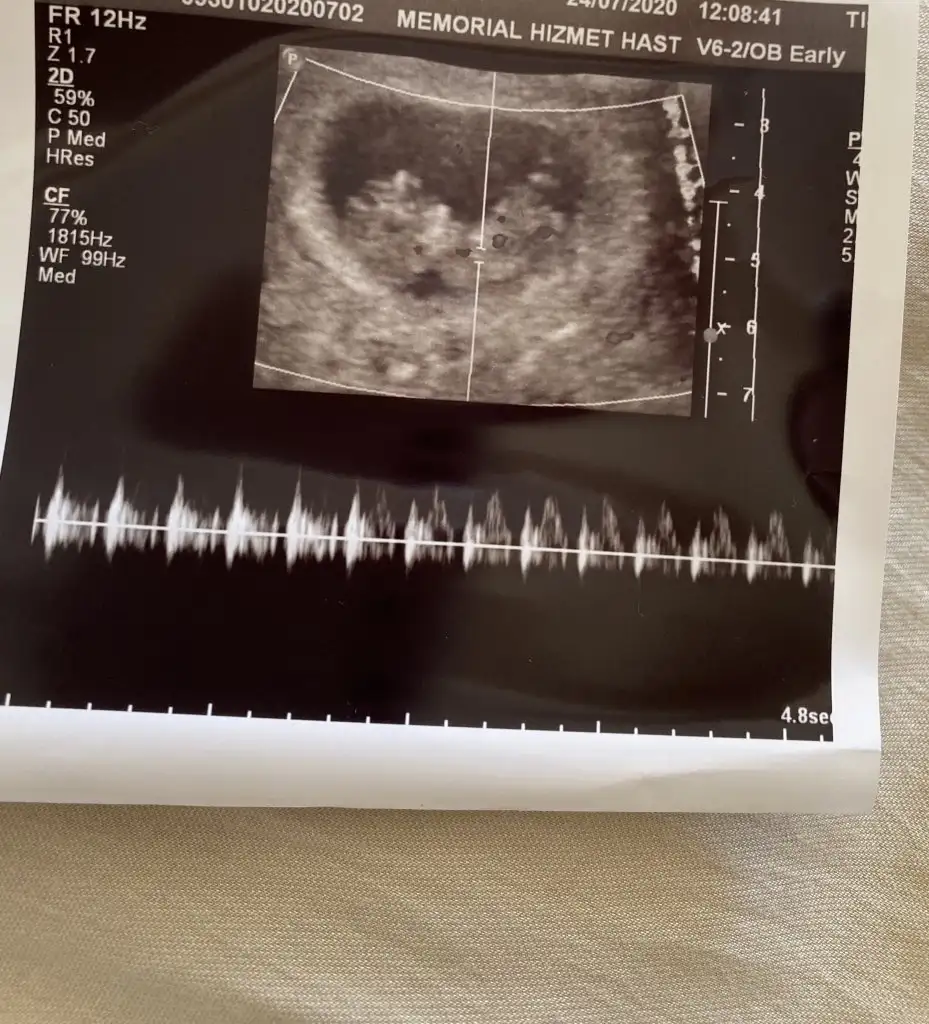

Merhaba cinsiyeti nedir sizce

Eklentiler

• A8851795-705C-44C5-8B8A-CCA8DB26E769.webp

A8851795-705C-44C5-8B8A-CCA8DB26E769.webp

80,4 KB · Görüntüleme: 64